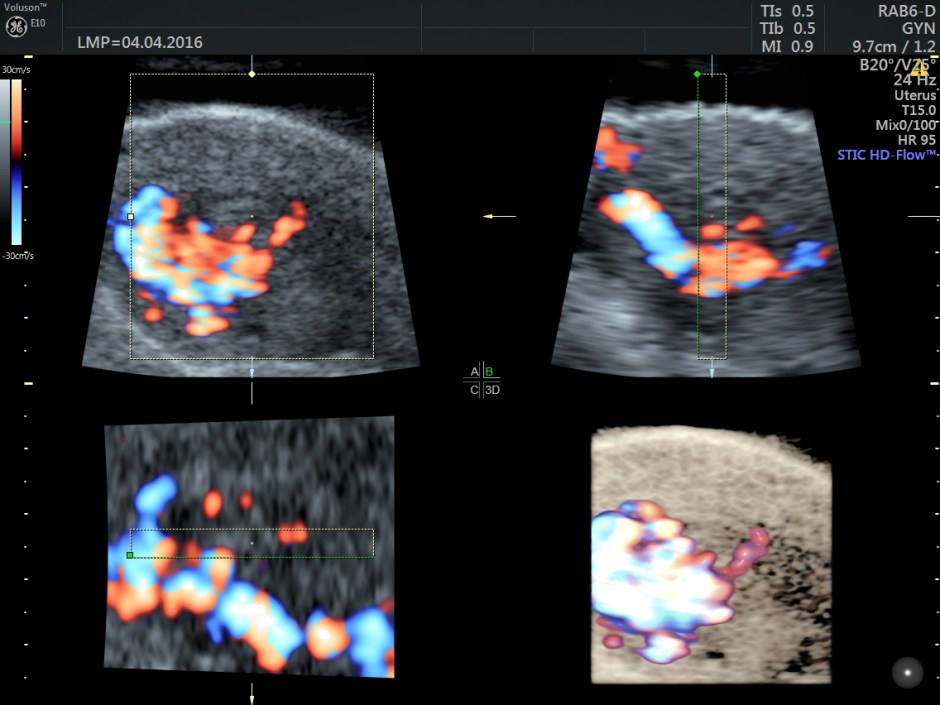

The following are the different sections of the Power Doppler reconstruction images of the trans-vaginal scan.

The following are the reconstructed 3D Power Doppler images.

For comparison a 2 d image is given below.